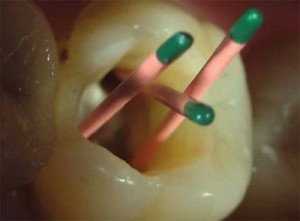

В эндодонтическом лечении зубов можно выделить 4 основных этапа:

1) обеспечение доступа к каналу;

2) удаление содержимого из канала и подготовка канала к пломбированию;

3)определение рабочей длины канала;

4) пломбирование канала инертным материалом, гарантирующим надежную герметизацию;